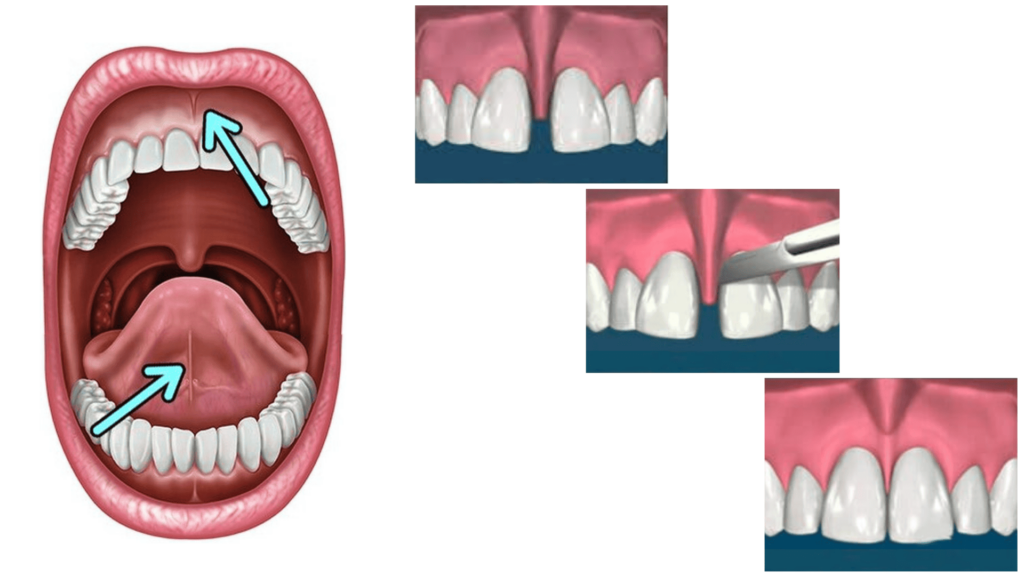

FRENULECTOMY

Frenulectomy is an oral surgical procedure in which the frenulum – the small fold of tissue located beneath the upper lip or tongue – is released.

The frenulum in the lower jaw can restrict tongue movement and impair speech, while in the upper jaw it can cause a gap between the front teeth (diastema) or gum recession.

The procedure is simple, painless, and brief.

The procedure is performed under local anaesthesia, and recovery is rapid and painless.